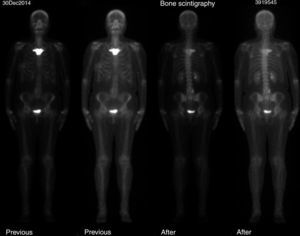

The study of the extension of the disease included BS, which revealed the presence of a diffuse blastic lesion in the sternal manubrium, suggestive of Paget's disease or a metastatic lesion (Fig. 1). The study was completed with radiographs of chest, lumbosacral spine and pelvis (Figs. 2 and 3), in which the only finding was increased density in L4-L5 facet joints. Chest CT, recommended by the professionals in nuclear medicine, revealed sclerosis in the sternal manubrium, suggestive of metastasis (Fig. 4).

Given the difficulty of the case, a clinical discussion session was held, with the participation of the departments of radiation oncology, rheumatology, radiodiagnostics and nuclear medicine, to review the findings. The outcome was a definitive diagnosis of SAPHO syndrome, as the patient met one of the inclusion criteria described by Benhamou et al.,5 hyperostosis of anterior chest wall, with or without dermal involvement, and none of the exclusion criteria (Table 1). A biopsy of the lesion was ruled out at that time, pending the radiographic evolution. The decision was made to perform BS and osteoarticular CT11 6 months later, at which time, no noteworthy changes were observed, and a biopsy of the affected area was definitively ruled out, as the images showed no signs of aggressive disease. During treatment, the patient required no analgesic medication of any type. We excluded the affected area from the field of treatment to avoid provoking modifications secondary to the radiotherapy that could lead to confusion when assessing the changes in the lesion. After 18 months of follow-up, the complete response of the tumor persists and the patient is disease-free.